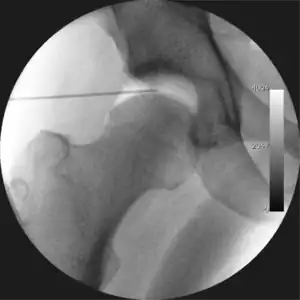

Figure 4. A needle is passed into the joint, breaking the 'suction seal', and allowing further distraction of the hip joint with minimal extra traction

The procedure is performed with the patient asleep (general anaesthetic) or under spinal anaesthesia. There are two widely used methods, one with the patient on their back (supine) and the other on their side (lateral decubitus). Which is used is down to the surgeon's preference. To gain access to the central compartment of the hip joint (between the ball and socket), traction is applied to the affected leg after placing the foot into a special boot. (See fig. 2) There is specifically designed equipment for this, although some surgeons use a 'traction table', initially designed to help in the operative fixation of broken thigh and lower leg bones. The amount of traction (or pull) needed is assessed with the help of fluoroscopy (low-dose portable x-ray). (See fig. 3) It is usually not possible to distract the ball from the socket with traction alone by more than a few millimetres. Once the surgeon is happy that they will be able to gain access to the hip joint (i.e. the ball will distract from the socket by a small amount), the patient is then painted with antiseptic and the surgical drapes applied.

The next step is to insert a fine needle under x-ray guidance into the hip joint. This breaks the 'suction seal' of the joint and allows further distraction if necessary (see fig 4). The surgeon wishes to see the ball move out the socket by approximately 1 cm, so that access to the hip joint can be achieved with minimal risk of damage to the joint surfaces. Most surgeons will inject fluid into the joint at this stage, again to ensure that there is enough space between the ball and socket for safe instrument access. This needle is then removed. The next step is placement of the 'portals', or the small holes made to pass instruments into the joint. This is achieved by again passing a fresh hollow needle into the joint under x-ray control, usually in a slightly different position. The reason for this is so the surgeon can ensure that the needle, and subsequent cannulae do not penetrate and damage the acetabular labrum or cartilage joint surfaces (see fig. 5). Again, surgeons will have their own preferences as to their preferred placement. Through this hollow needle, a long thin flexible guide wire is passed into the joint, and the needle is removed over it, leaving the guide wire in situ. A small cut in the skin is made around the wire, to allow for larger cannulae to be placed over the wire through the portal. The wire therefore guides the larger cannulae into the joint. The most common external diameters of cannulae used are between 4.5 and 5.5 mm. Once the surgeon is satisfied that the cannula is in the correct position, by a combination of feel and x-ray guidance, the guide wire can be withdrawn. Once the first portal is correctly placed, any further portals may be created once the camera is in position, to ensure that they are placed with minimal risk to the joint surfaces. This process can be repeated to gain as many points of entry to the hip joint as the surgeon requires, normally between two and four. Certain of these entry points will be used for the viewing arthroscope and others for operating instruments.